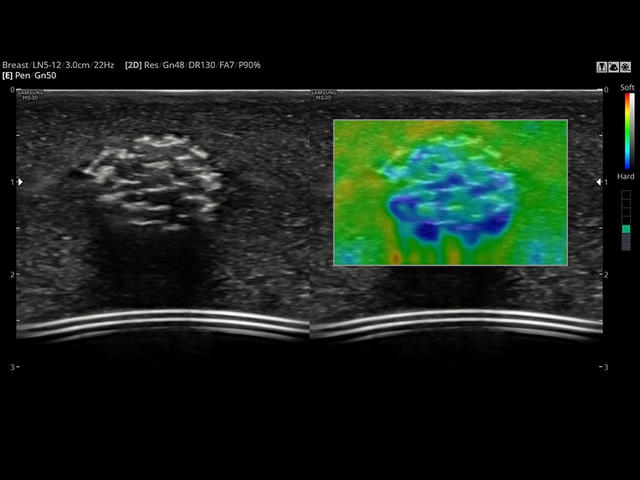

- Модуль Elastoscan - программы эластографии (качественная оценка) для исследований щитовидной железы, молочной железы у женщин и предстательной железы у мужчин.